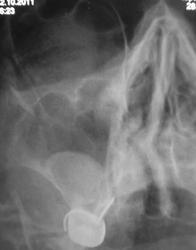

Пол пациента: Женский пол Тип патологии: Другое Область исследования: Челюстно-лицевая область и шея Методы исследования: Rg Пациент направлен отоларингологом на рентгенографии ППН. https://radiomed.ru/sites/default/files/styles/case_slider_image/public/user/12/2.pa130017.jpg?itok=v1ahIvCO https://radiomed.ru/sites/default/files/styles/case_slider_image/public/user/12/3.pa130018.jpg?itok=g_2UjqAl https://radiomed.ru/sites/default/files/styles/case_slider_image/public/user/12/4.pa130019a.jpg?itok=7_1J-Lyl ID:16132 Чт, 13/10/2011 - 20:10 #1 ДокRg Не на сайте Был на сайте: 12 лет 3 месяцев назад Зарегистрирован: 30.03.2011 - 20:05 Публикации: 105 Доброго времени суток уважаемые пользователи и гости сайта, моё мнение - одонтогенная киста правой в/ челюстной пазухи. Чт, 13/10/2011 - 20:16 #2 ДокRg Не на сайте Был на сайте: 12 лет 3 месяцев назад Зарегистрирован: 30.03.2011 - 20:05 Публикации: 105 и еще искривление носовой перегородки. Пт, 14/10/2011 - 18:48 #3 stovbav Не на сайте Был на сайте: 2 года 2 месяцев назад Зарегистрирован: 20.12.2009 - 17:28 Публикации: 7066 Согласен с коллегой...да и вспомнились высказывания на предмет не писать об искривлении перегородки...и как вот в ТАКОМ случае не написать? Болезни ног: виды, симптомы, причины, профилактика и лечение Пт, 14/10/2011 - 19:28 #4 Makcimalist Не на сайте Был на сайте: 11 лет 8 месяцев назад Зарегистрирован: 08.05.2010 - 14:28 Публикации: 1994 stovbav wrote: Согласен с коллегой...да и вспомнились высказывания на предмет не писать об искривлении перегородки...и как вот в ТАКОМ случае не написать? - Согласен! Считаю, нужно описывать такие отклонения от нормы! -------------- "Просто, по видимости, не видеть логики в очевидных вещах - это тоже одно из свойств некоторых умов, наряду с грустными думами о свойствах ума других." © Vega 08/10/2011 Пт, 14/10/2011 - 21:28 #5 Катенёв Валенти... Не на сайте Был на сайте: 7 лет 2 недели назад Зарегистрирован: 22.03.2008 - 22:15 Публикации: 54876 А, киста, прям - Венера Милосская!

Доброго времени суток уважаемые пользователи и гости сайта, моё мнение - одонтогенная киста правой в/ челюстной пазухи.

и еще искривление носовой перегородки.